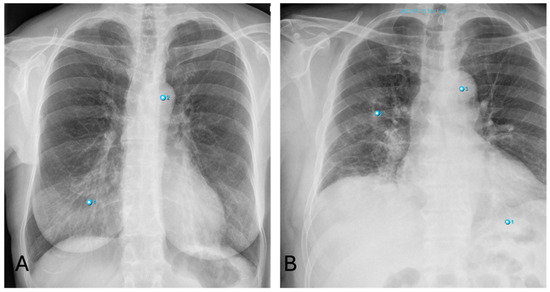

3.4.2. Pneumonia

False-positive AI findings occur in younger patients with dense breast tissue, as well as with increased vascular markings indicative of congestion (Figure 6A). The AI also frequently interprets poorly defined lung masses as pneumonic infiltrates.

False-negative results for pneumonia often occur in cases of early pneumonic infiltration or when the infiltrates are located retrocardially. Similarly, pneumonia near the hilum is frequently undetected by the software (Figure 6B).

3.4.3. Nodules

Besides fractures, the detection of lung nodules also shows high discrepancies between software and human raters. Smaller nodules are sometimes overlooked by radiologists (Figure 7B), whereas pseudo-lesions—structures such as nipple shadows, catheter material or port needles as well as external foreign bodies—are sometimes falsely interpreted as pulmonary nodules by the AI (Figure 7D). These pitfalls occur only seldom with radiologists, who can easily correctly identify these items for what they really are. Similarly, transversely sectioned vessels or bronchi are diagnosed as round opacities indicative of pulmonary nodules due to their morphology. For pleura-adjacent nodules, the distinction from pleural plaques is not always clear.

False-negative findings occur, for example, due to the misinterpretation of a pulmonary nodule as pneumonia because of overlapping morphology. Additionally, the diagnosis of masses in the lingula segment of the lung is complicated by the overlap with the heart.

Figure 6. Inconsistencies of pneumonia diagnoses: (A)—false-positive AI interpretation of dense breast parenchyma as pneumonia in a young woman (Note: other finding incorrectly labelling “aortic abnormality”); (B)—false-negative interpretation of pneumonia. X-ray shows pneumonic congestion in the right lower lobe not detected by AI (Note: other findings incorrectly labelling “aortic abnormality” and “pneumonia”).

Figure 7. Inconsistencies of nodule diagnoses: (A)—false-positive AI interpretation of pulmonary mass in the lower lobe on the left as infiltration caused by pneumonia. (Note: Also false classification of Portcatheter as pneumothorax, again “aortic abnormality” and “rip fracture”); (B)—correctly identified nodule by AI overlooked by radiologist (Note: other finding incorrectly labelling “aortic abnormality”); (C)—False-positive nodule described by AI, really corresponding to the overlay of two ribs; (D)—False-positive nodule described by AI, really corresponding to external oxygen hose (Note: other findings incorrectly labelling “aortic abnormality” and “rib fracture”).